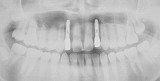

歯列矯正 歯肉形態修正手術 インプラント メタルボンドを併用した症例です。

この治療では1本の歯も削ったり、抜いたりはしていません。

- 先天的に上顎側歯列が欠如している患者さんです。

- はじめに矯正治療を行い、本来歯があるべき位置に矯正して、インプラント手術のためのスペースを確保しました。

- 矯正治療終了後に歯肉の形態修正手術を行いました。

- 本来の側切歯部分にインプラント埋入

- メタルボンドにて修復